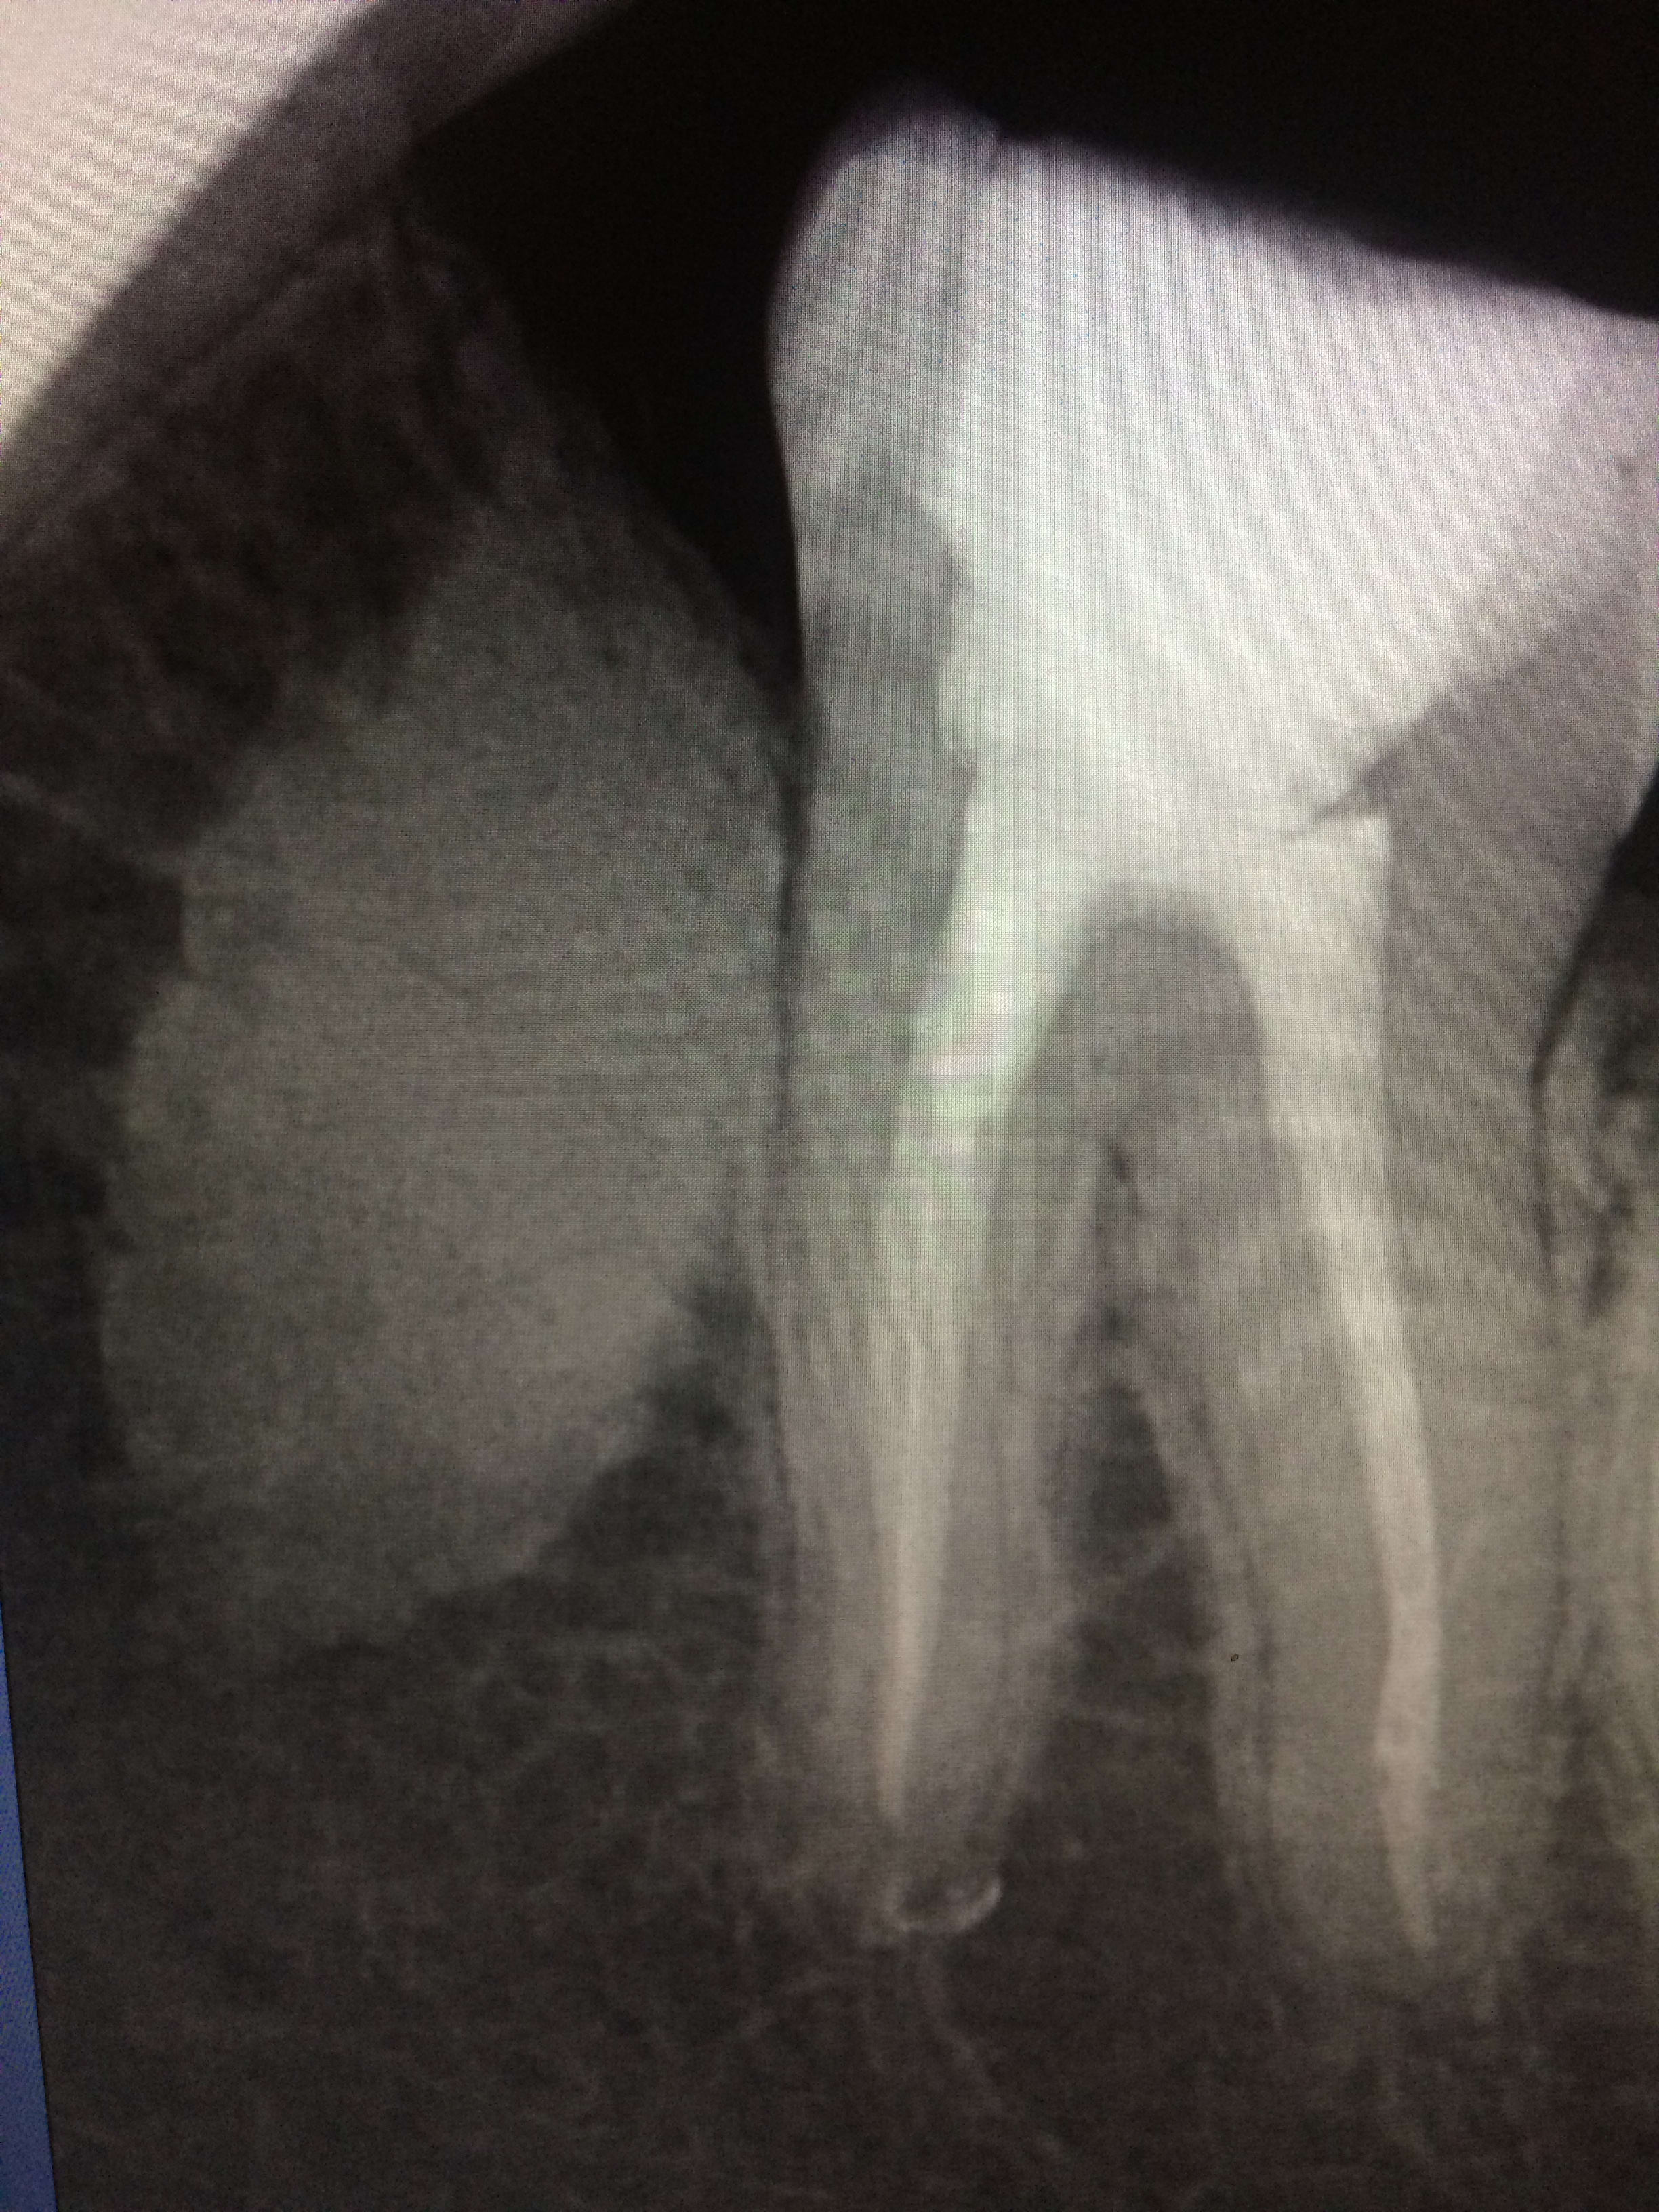

Auriez vous une idée sur l’image en M de 37 ?

Actuellement asymptomatique.

Codensation osseuse.....

Perso j'adresserai aà sto au cas où...